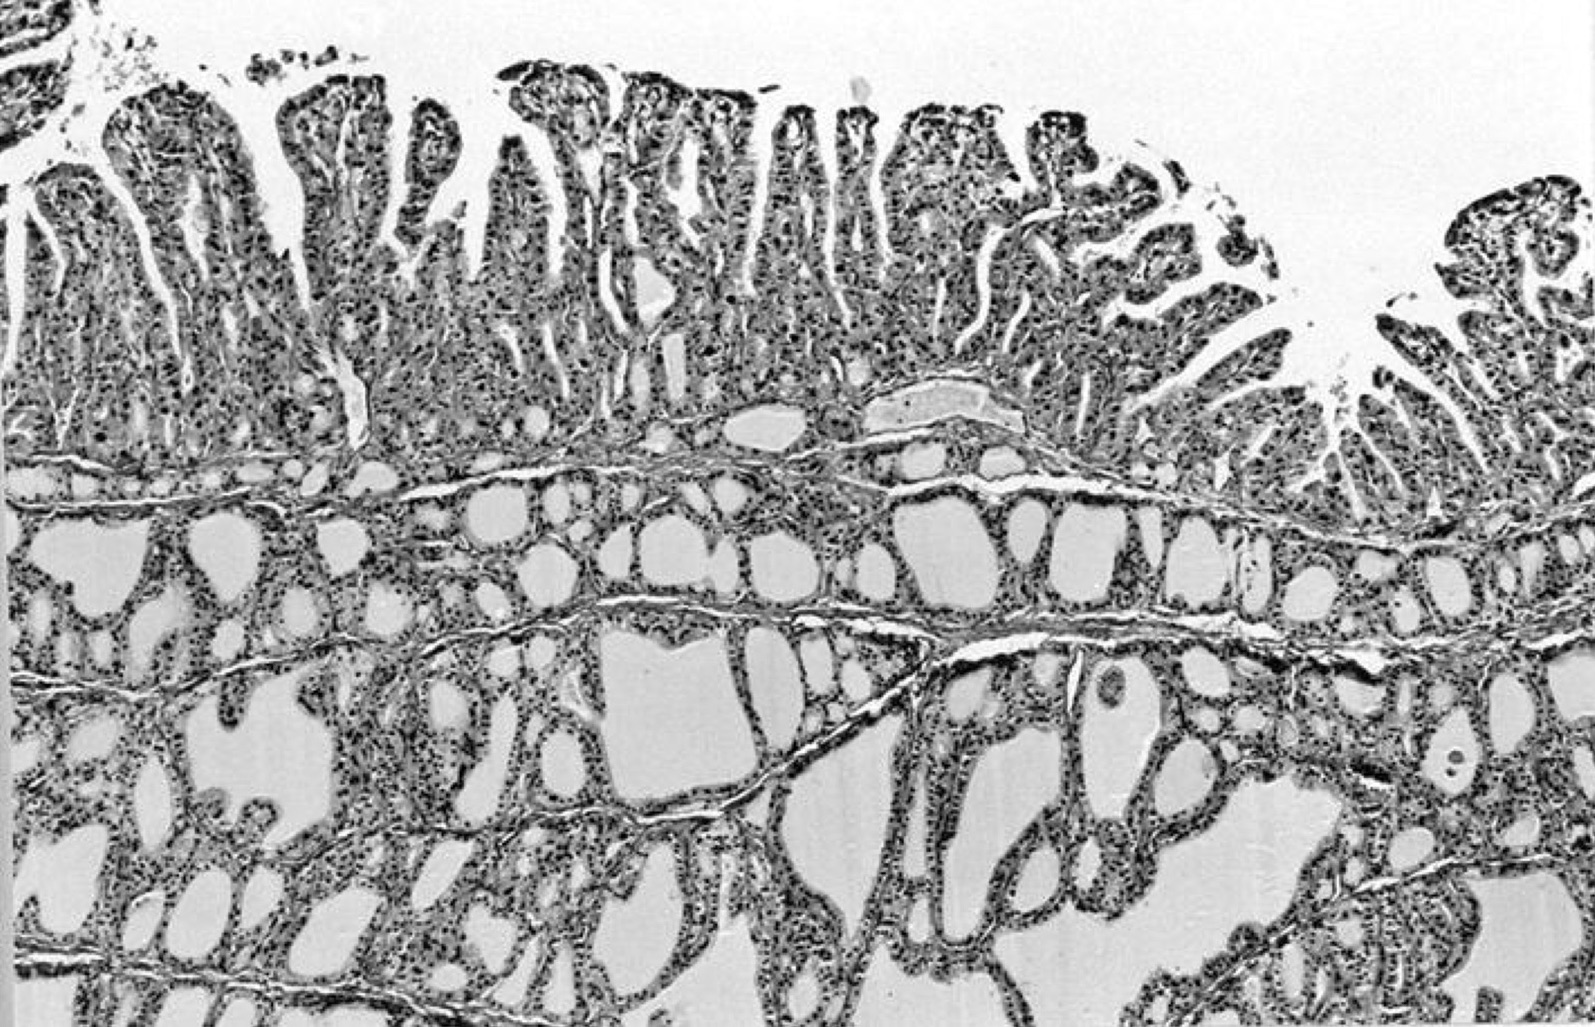

Microscopic (histologic) description

- Variable sized dilated follicles with flattened to hyperplastic epithelium

- Nodules may be present but without thick capsule

- Nodules with variable histological patterns: from colloid and microfollicular to hypercellular / microfollicular

- Secondary changes may be seen, including foci of fresh or old hemorrhage, rupture of follicles with granulomatous response, fibrosis, calcification and even osseous metaplasia

- Some of the cystically dilated follicles may show papillary projections (Sanderson polsters) that may mimic papillary carcinoma; however, they lack the nuclear features of papillary carcinoma

Microscopic (histologic) images

Contributed by Swati Satturwar, M.D., Andrey Bychkov, M.D., Ph.D. and Rajeshwari K. Muthusamy, M.D.

AFIP images